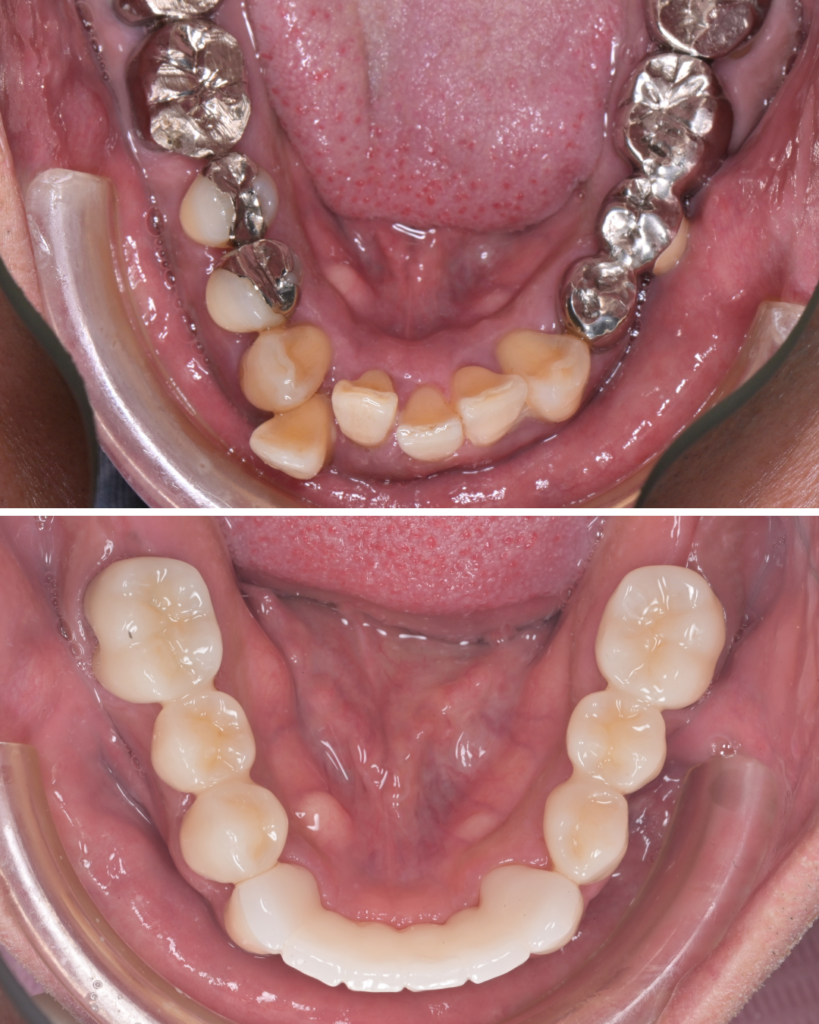

50代 歯周病 セラミック治療 ビフォーアフター

歯周病で歯がグラグラしていたため、歯列矯正は行わず、歯の状態を優先してセラミック治療を選択した50代の症例です。

歯を連結することで安定性を確保

- グラグラしている前歯は、セラミックで連結

- 見た目だけでなく、噛む力を分散し安定させる目的

歯並び・色・形を同時に改善できる

- ガタガタ

- 歯の長さの不揃い

- 被せ物の色の違い

を一度の治療計画で改善できるメリットがありました。